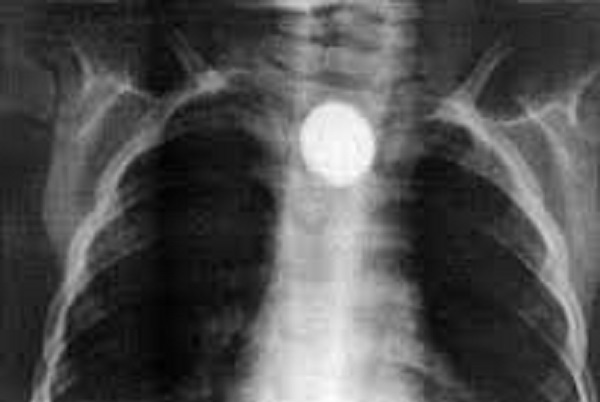

foto 8 mesyachnyj rebenok proglotil monetu hirurgi ee izvlekli elgezit